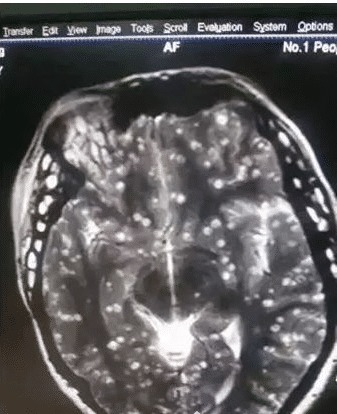

经过检查,小婷全身都疼痛,是因为体内的虫子,影像显示她的大脑和眼球背部,还有腹部等到处长满了虫子,可以这么说吧,小婷现在就像案板上的肉。了解后知道小婷是南方的一个村里的人,当地习俗是每年年底家里都会杀猪,请来屠夫,猪身上最嫩的肉,会被送东家当头彩。将这块肉片好,然后蘸料生吃。

小婷这种情况应该挺久的,但是自没在意,现在杀死了寄生虫,还是会有钙化现象。虫子要是钙化了,病情就会加重。如果在大脑里面钙化了,容易智力下降,瘫痪等各种严重问题。小婷必须立马治疗不能耽搁。